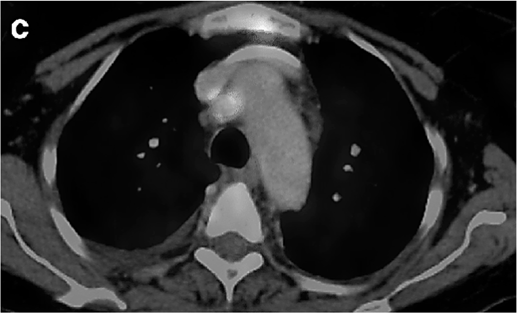

Um paciente de 62 anos de idade, tabagista ativo, cerca de 180 anos-maço, queixa-se de cansaço, tosse seca e perda de peso; por isso, procurou atendimento médico. O paciente referiu que pesava 100 kg e perdeu 10 kg. Realizou-se tomografia computadorizada de tórax, com evidência de lesão sólida de 2,1 cm em topografia de lobo inferior à direita, sólida, espiculada, com margens bem definidas e densidade de partes moles, assim como linfonodomegalia paratraqueal direita de 1,5 cm, paratraqueal esquerda de 1,2 cm e subcarinal de 2 cm. O paciente foi submetido a PET-CT de corpo inteiro, com evidência de hipercaptação de radiofármaco pela lesão (SUV 12) e pelo linfonodo representado na figura 2 a seguir.

Figura 2: PET-CT do tórax.